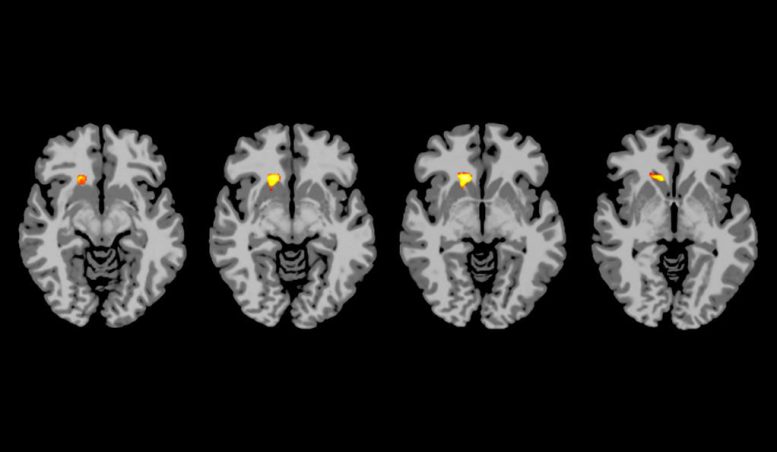

为了调查原因,由耶鲁大学领导的团队对1型糖尿病的个体和接受胰岛素诱导低血糖的健康成年人进行了MRI扫描。脑部图像显示,在健康的个体中,低血糖会导致大脑四个关键区域的变化,这些变化与奖励,动机和决策制定有关。

相比之下,大约一半的1型糖尿病患者仅在与注意力有关的大脑区域表现出活动改变。其余的糖尿病患者即使对轻度低血糖也没有表现出任何大脑变化。